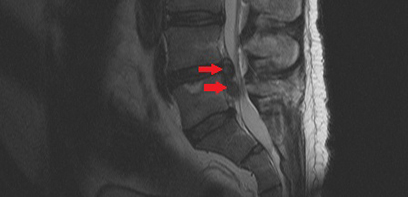

In a Canadian first, surgical team at London Health Sciences Centre performs robotic assisted spinal surgery

April 26, 2024

The team, led by Schulich Medicine & Dentistry’s Dr. Victor Yang, completed a successful, robotic-assisted direct lateral spine surgery.